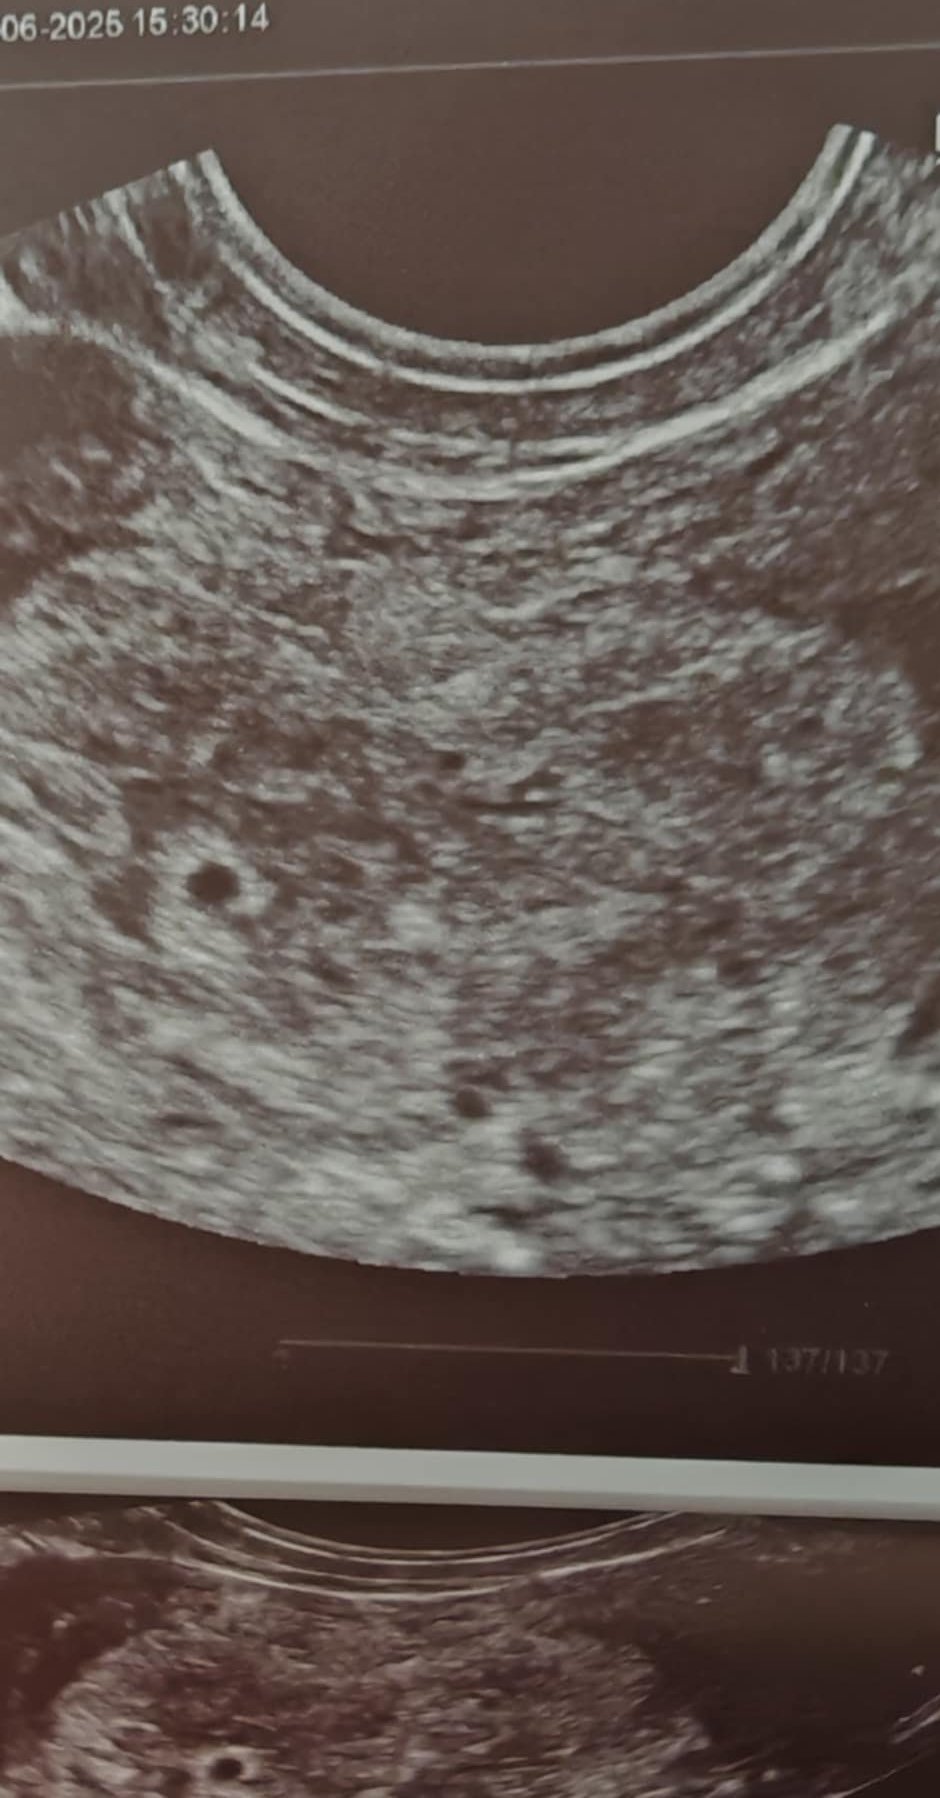

Момичета, прибрах се.

Не се възцари голяма яснота, но според доктора е 95% вътрематочна, вижда на едно място удебелена лигавица и има съмнения, че това може да е плоден сак. Това е най-зумнатия и ясен кадър на удебелението:

Скрит текст:

Но на диагнозата си ми написаха неуточнена, извънматочна бременност, докато не се докажела вътрематочна.

Чхг излезе току що:

понеделник сутринта 584

днес късен следобед 934

Преди това беше 3 дена в плато, знаете.

Ще проследя чхг и в петък рано рано и после ме вика да ме погледне пак.

А утре сутринта ще отида и в Надежда. Надявам се Тихомирова да ми огледа тръбите хубаво, защото днес Дойчиновски каза, че нямало как да се види дали е там на този етап и не се мъчи изобщо.

Edit: изчислих времето на удвояване - 80 часа, което продължава да е притеснително.

Тирамису, според мен е вътрематочна. Това си е сак, който за 930 чхг си изглежда ок. Не знам защо да го писали така на диагноза .... Чхг върви почти правилно , ясно е че не е бетонирано удвоение, но съм виждала и по-бавно растящи чхг-та по групите. Стискам палци, според мен това са добри новини!

Тирамису, изглежда обнадеждаващо, вижда се ясно тази точица, дано това е сакчето и всичко да се развие благополучно! Чгх расте добре 🤗